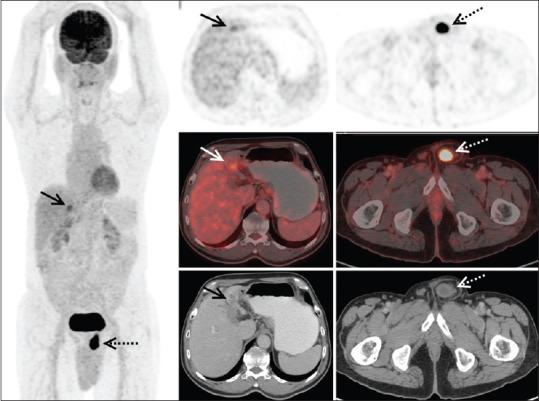

Incidental Detection of Urinary Bladder Herniation in F-Fluorodeoxyglucose Positron Emission Tomography/Computed Tomography Mimicking as Metastatic Deposit in the Inguinal Canal.

Although F-fluorodeoxyglucose (FDG) is the most extensively used tracer in oncological positron emission tomography/computed tomography (PET/CT) studies, various physiological as well as benign pathological conditions are known to cause false-positive results. This report describes F-FDG PET/CT done in an elderly man with primary hepatocellular carcinoma, revealing a metastasis mimicking lesion in the left inguinal canal, which was identified as the herniated portion of the urinary bladder. Though rare, bladder herniation, especially with a narrow neck, can be a pitfall in the evaluation for metastatic disease. The study also highlights the utility of delayed imaging in the evaluation of pelvic pathology.